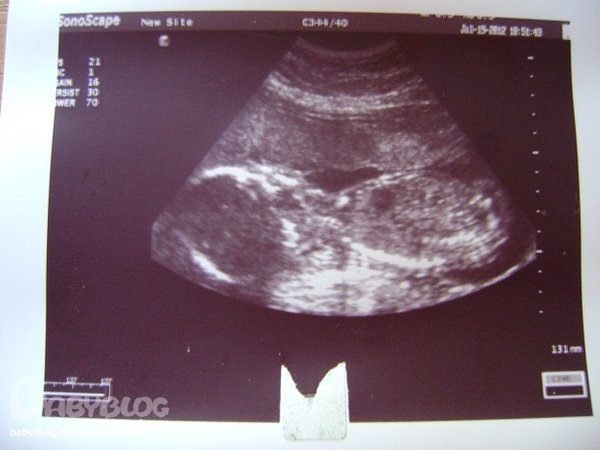

слева голова,справа туловище-если честно не очень видно и понятно,зато сердечко видно))